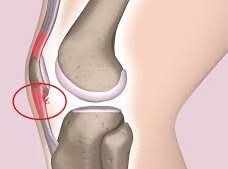

Xương bánh chè là một đoạn xương nhỏ nằm ở trước khớp gối. giúp chân di chuyển, đứng thẳng bằng cách giảm áp lực lên khớp gối. Gân bánh chè là một dải mô nối xương bánh chè với xương chày.

Gân bánh chè đóng vai trò cực kỳ quan trọng, phối hợp với các cơ ở phía trước đùi (cơ tứ đầu) để giúp chúng ta duỗi chân. Chức năng này cho phép bạn thực hiện các hoạt động hàng ngày như đá bóng, đạp xe, và đặc biệt là các động tác bật nhảy.

Viêm gân bánh chè gây đau ở vùng phía trước đầu gối, ngay bên dưới xương bánh chè.